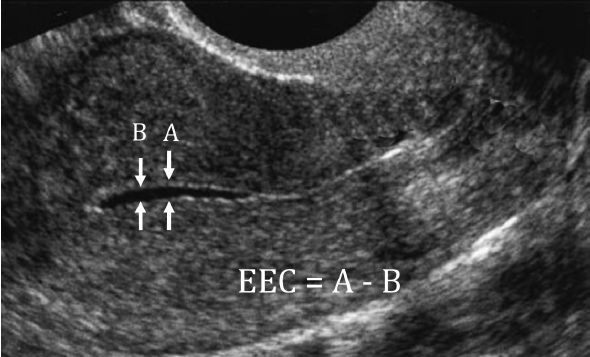

子宫内膜增生